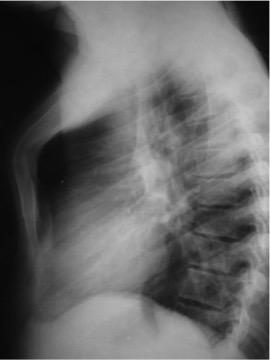

CASO: Febrícula y tos de 4 días de evolución.

Hallazgos:

- En la placa PA se observa una asimetría en los hilios pulmonares, el hilio izquierdo tiene una densidad aumentada.

- Tras examinar la placa lateral se observa un aumento de densidad en la columna que puede ser compatible con una condensación, es el signo de la desnificación vertebral.

SIGNO DE LA DENSIFICACIÓN VERTEBRAL: En la radiografía lateral normal, la densidad de la columna torácica tiende a disminuir desde la parte superior hasta el diafragma; la alteración de ese patrón por la presencia de una densidad superpuesta a la columna, indica la existencia de una consolidación pulmonar. Este signo adquiere especial valor cuando en la proyección posteroanterior la consolidación está oculta en el espacio retrocardíaco o en la base pulmonar.